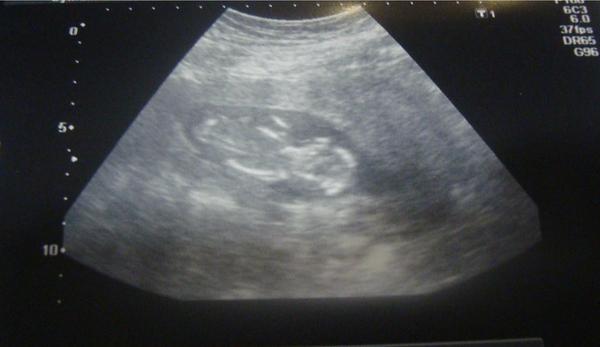

@lylkatomaskova toto je fotka z 12.týždňa a určite sa oplatí 😉

@lylkatomaskova ahoj,urcite sa to oplati,ak ho pan doktor dobre odfoti 🙂 vidiet rucicky,nozicky,dokonca co mam videozaznam zo sona,vidiet detailne aj prstiky na nozicke...je to uzasne 🙂